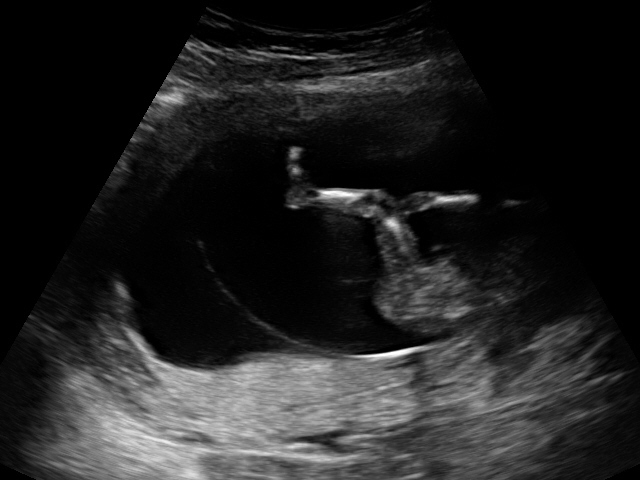

So neugierig :) Würde gerne eure Meinung lesen :) Geschlecht? Mädchen oder Bub?

Hallo!!Bin in der 15SSW. Diese Fotos entstanden bei der Nackenfaltenmessung und die Ärztin wollte mir keine Tipp geben, obwohl Freundinnen von mir alle eine Meinung des Arztes erhalten haben. Naja vielleicht erkennt ihr ja da was :) Danke. LG

Ich glaub das wird ein Bub ;)

Jedoch is es am bild 3 schwer zu erkennen.....

• Hm ich könnte höchstens am Bild 3 was erahnen aber auch nicht wirklich. Sind das alle Bilder die du hast? In welcher Woche warst du da? Bei der NFM ist halt noch sehr früh.

• Das war 14SSW :)

• In der 14.SSW erkennt man frühestens einen deutlichen Unterschied zwischen Junge und Mädchen. Vorher gibt es wohl Unterschide im Geschlechtshöcker aber schwer. Bei mir war es so, dass der Arzt in der 14.SSW in der erste Ss deutlich einen Jungen erkannt hat und ich selber es sigar deutlich sehn konnte. Bei meiner Tochter meinte er, er sieht momentan eine steirische Semmel aber es wäre noch wie Kaffeesatz lesen und es ist einfach noch zu früh. Hast du selber nichts erkannt obder geglaubt was zu erkennen?

• Auf bild 4 würde ich an Buben sehen ;-)